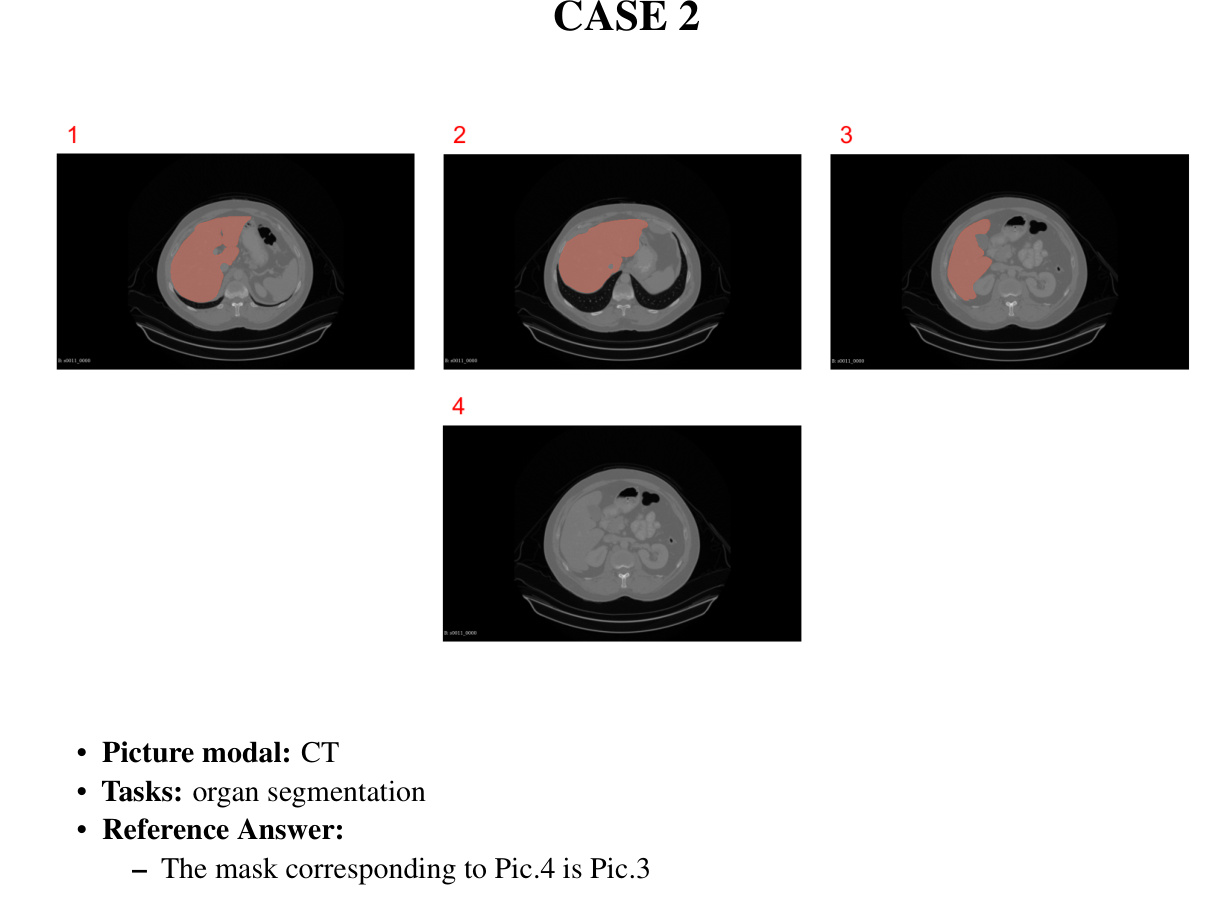

6.3.2 Case 2: CT mask-organs matching challenge

CASE 2 Control Group

案例2 对照组

Prompt: Please tell me which mask at the top corresponds to the liver below, consider the red part only.

提示:请告诉我上方哪个遮罩对应下方的肝脏,仅考虑红色部分。

GPT-4V Response:

GPT-4V 响应:

CASE 2

案例 2

Step-by-step guidance (single round)

分步指南(单轮)

Step-by-step guidance (multi-round)

分步指导(多轮)

Prompt 1: Picture 123 is the mask template for the liver(the red part), and Picture 4 is an image of an abdominal CT section, please tell me the location and size of the liver in picture 4.(answer in 50 words)

提示1:图123是肝脏的掩模模板(红色部分),图4是一张腹部CT切片的图像,请告诉我图4中肝脏的位置和大小。(回答限50字)

Prompt 2:Please tell me the location and size of the livers in picture 1 2 3 (answer in 50 words) Prompt 3:Which mask would correspond to Picture 4 (answer in 50 words)

提示2:请告诉我图片1、2、3中肝脏的位置和大小 (回答限50字)

提示3:哪张遮罩(mask)对应图片4 (回答限50字)

• response 1:

• 响应1:

– Answering prompt 1: In Picture 4, the liver is located in the upper right quadrant of the abdominal cavity, extending across the midline to the upper left quadrant. It is the large, dark gray area beneath the diaphragm. The size cannot be accurately determined without specific measurements or scale, but it occupies a significant portion of the upper abdominal area.

- 回答提示1: 在图4中,肝脏位于腹腔右上象限,延伸跨过中线至左上象限。它是横膈膜下方的大片深灰色区域。由于缺乏具体测量数据或比例尺,无法准确判断其大小,但可见其占据了上腹部相当大区域。

– Answering prompt 2: In Pictures 1, 2, and 3, the liver (highlighted in red) is primarily located in the right upper quadrant of the abdominal cavity. The size appears large, spanning across to the left upper quadrant, below the diaphragm. Without a scale, precise size cannot be determined, but it occupies a substantial portion of the abdominal cavity in each image.

回答提示2:在图1、图2和图3中,肝脏(用红色高亮显示)主要位于腹腔的右上象限。其体积显得较大,横跨至左上象限,位于横膈膜下方。由于缺乏比例尺,无法确定精确尺寸,但在每张图像中它都占据了腹腔的相当大部分。

– Answering prompt 3: Picture 1’s mask seems to cover the largest area, extending quite far to the left, which might be too large for Picture 4. Picture 2’s mask has a more confined area on the right side, which may not cover all of the liver in Picture 4. Picture 3’s mask is in between the two in terms of coverage, possibly being a closer match to the liver in Picture 4. Based on this visual assessment, Picture 3’s mask might correspond most closely to the liver in Picture 4.

- 回答提示3:图1的遮罩覆盖区域似乎最大,向左延伸较远,可能对图4来说过大。图2的遮罩在右侧区域较为局限,可能无法覆盖图4的全部肝脏。图3的遮罩在覆盖范围上介于两者之间,可能更接近图4的肝脏。基于此视觉评估,图3的遮罩可能与图4的肝脏匹配度最高。

• response 2:

• 响应 2:

– Answering prompt 1: The liver in Picture 4, based on the mask template provided in Pictures 1-3, is not delineated with a red mask. However, typically, the liver is located in the upper right quadrant of the abdomen in a CT image, extending from just under the diaphragm down towards the right kidney. It is not possible to accurately determine the size of the liver from Picture 4 without the mask, but the liver is usually the largest solid organ in the abdominal cavity

回答提示1:图4中的肝脏,基于图1-3提供的掩膜模板,并未用红色掩膜勾勒出来。然而通常情况下,在CT图像中肝脏位于腹部右上方,从横膈膜下方延伸至右肾附近。由于缺乏掩膜,无法从图4中准确判断肝脏大小,但肝脏通常是腹腔内最大的实体器官

Answering prompt 2: In pictures 1, 2, and 3, the liver (highlighted in red) occupies the upper right quadrant of the abdomen. It extends across the midline to the left upper quadrant. The size appears substantial, filling much of the space below the diaphragm and above the stomach and intestines.

回答提示2:在图1、图2和图3中,肝脏(红色高亮部分)位于腹部右上象限,并向左上象限延伸跨过中线。其体积较大,占据了膈肌下方与胃、肠上方的大部分空间。

– Answering prompt 3: Based on typical anatomical position and the visible structures in Picture 4, the liver mask that would correspond most closely appears to be the mask in Picture 1, considering the liver’s location and the visible vas cula ture branching within the liver tissue.

回答提示3:根据标准解剖位置和图4中可见结构,考虑到肝脏的位置及肝组织内可见的血管分支,与之最匹配的肝脏掩膜应为图1中的掩膜。

• response 3:

- response 3:

Answering prompt 1: In Picture 4, the liver is located in the upper right quadrant of the abdomen, just below the diaphragm. It spans from the right side across the midline towards the left, extending slightly past the stomach. The size of the liver appears to be within normal limits, occupying a significant portion of the upper abdominal cavity.

回答提示1:在图4中,肝脏位于腹部右上象限,紧贴横膈膜下方。它从右侧跨越中线向左延伸,略微超过胃部。肝脏大小显示在正常范围内,占据了上腹腔的显著部分。

Answering prompt 2: In Pictures 1-3, the liver, indicated by the red mask, occupies the upper right quadrant of the abdomen, extending across the midline to the upper left quadrant. It varies in size across the images, with Picture 2 showing the largest coverage and Picture 3 showing the least.

回答提示2:在图1-3中,红色遮罩标示的肝脏位于腹部右上象限,并跨越中线延伸至左上象限。各图中肝脏大小不一,图2显示覆盖范围最大,图3显示覆盖范围最小。

– Answering prompt 3: Without medical imaging software to analyze the images in detail, it’s challenging to accurately determine which mask corresponds to Picture 4. However, based on visual approximation, Picture 1 appears to have a liver mask that most closely matches the visible liver contours in Picture 4.

- 回答提示3:在没有医学影像软件详细分析图像的情况下,很难准确判断哪张掩膜对应图4。但通过视觉近似对比,图1的肝脏掩膜与图4中可见的肝脏轮廓最为接近。